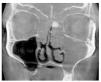

Figura 4. Tomografía volumétrica digital dental: plano coronal.

En la TVD se observa un seno maxilar izquierdo íntegro y homogéneamente ocupado, además de una obstrucción del ostium fisiológico en ambos lados. Se aprecia también una opacificación subtotal de todo el complejo etmoidal y también del seno frontal. Estos hallazgos sugieren un diagnóstico de mucocele del seno maxilar izquierdo y de pansinusitis de los senos paranasales. En el lado izquierdo, en la zona de las celdas etmoidales superiores se observa una masa circunscrita de densidad similar a los tejidos duros junto con una obstrucción parcial de las celdas etomoidales izquierdas. Se trata probablemente de un osteoma.